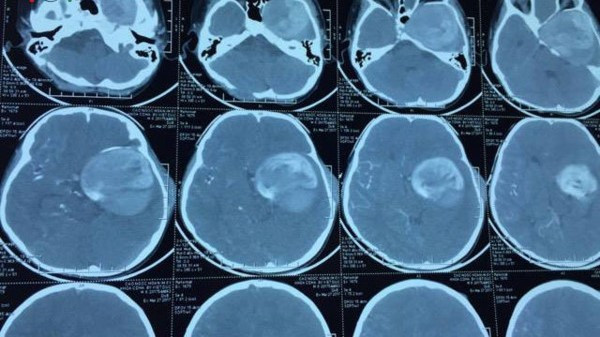

Hình ảnh khối phình động mạch cảnh trong khổng lồ, ảnh do Bệnh viện Việt Đức cung cấp

Bệnh nhân quê ở Quảng Bình, nhập viện ngày 3/6 trong tình trạng bị phình động mạch cảnh trong khổng lồ, kích thước 10 x 12cm. Đây là trường hợp hiếm gặp, vì bình thường, túi phình chỉ có kích từ 1,5 đến 2,5 cm. Túi phình này phát sinh do dị dạng của thành mạch máu và áp lực của dòng chảy, chèn ép trực tiếp vào dây thần kinh thị giác, khiến bệnh nhi bị mất thị lực hoàn toàn. Ngoài ra, bệnh nhi còn bị phình mạch ở động mạch dưới đòn phải, động mạch thận trái và động mạch cánh tay phải. Nếu không được can thiệp kịp thời sẽ có nguy cơ tử vong.